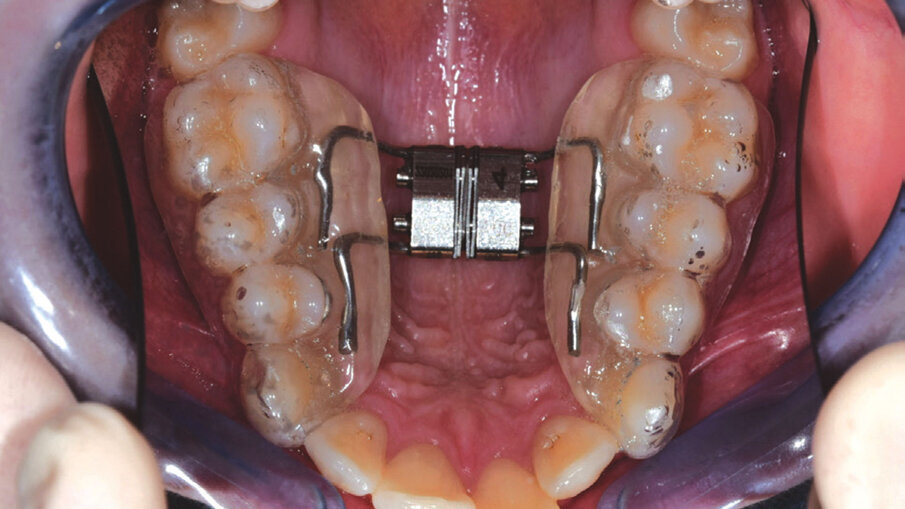

Questo successo ha spinto i produttori a migliorare le caratteristiche dei propri allineatori (materiali, spessore, termoformatura) e introdurre l’utilizzo di dispositivi ausiliari (Figg. 1a-2c) (espansori, bite-ramp, tagli di precisione, elastici), allo scopo di aumentare la predicibilità degli spostamenti dentali ottenibili e la tipologia delle malocclusioni da trattare1-5. Nonostante l’enorme mobilitazione di risorse finanziarie in tutto il mondo, finalizzate alla produzione di nuove linee di prodotti, sono pochi gli studi clinici e le prove di alta qualità sulla reale efficacia di tale trattamento, per stabilire l’affidabilità concreta degli allineatori dentali nella terapia ortodontica; sappiamo sicuramente che la durata di trattamento e il tempo alla poltrona ridotti sembrano essere vantaggi sostanziali degli allineatori rispetto ai sistemi convenzionali, oltre ad assicurare una migliore estetica, un grande comfort, un più facile mantenimento dell’igiene orale e una migliore salute parodontale. Tuttavia, sulla base dell’attuale evidenza scientifica disponibile, la terapia con allineatori dentali è efficace soprattutto nella gestione di malocclusioni lievi e mostra risultati accettabili per il trattamento di malocclusioni moderate6.

Figg. 2a-2c_Utilizzo del dispositivo ALLEO+ come ausiliare per espandere e ottenere spazio in arcata superiore, al fine di utilizzare, successivamente, un numero di allineatori ridotto e una minore quantità di stripping.

Figg. 2a-2c_Utilizzo del dispositivo ALLEO+ come ausiliare per espandere e ottenere spazio in arcata superiore, al fine di utilizzare, successivamente, un numero di allineatori ridotto e una minore quantità di stripping.

Figg. 2a-2c_Utilizzo del dispositivo ALLEO+ come ausiliare per espandere e ottenere spazio in arcata superiore, al fine di utilizzare, successivamente, un numero di allineatori ridotto e una minore quantità di stripping.